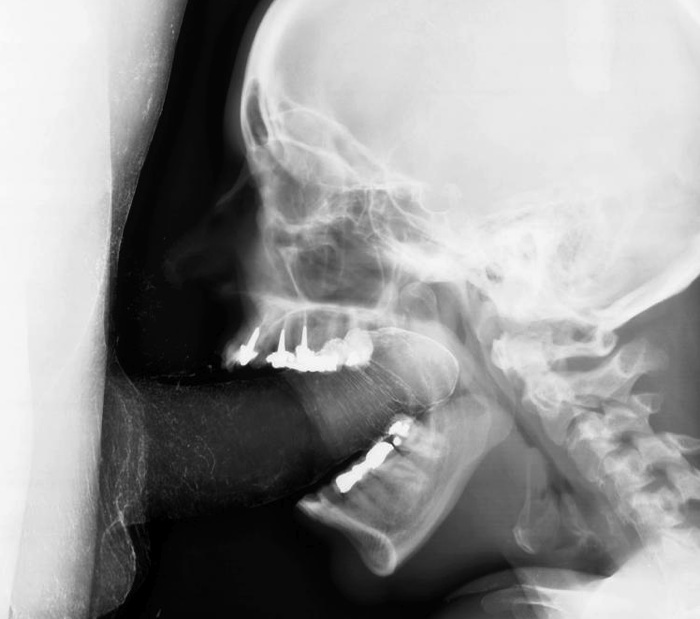

А что за дырка во лбу?Так должно быть или это след от трепанации?)

Я бы лучше спросил, что у неё с зубами 8-)

N'urk (09:59), он это или она еще надо подумать, а вот на счет дырки во лбу - так это пазухи у всех полов присутствуют, у этого персонажа еще и гайморит : )))))

почти на всех зубах пломбы, некоторые с рутканалами :)